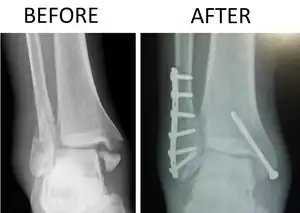

| X-ray of trimalleolar fracture repair before and after ORIF surgery | |

A trimalleolar fracture also known as Cotton fracture,[1] is a fracture of the ankle that involves the lateral malleolus, the medial malleolus, and the distal posterior aspect of the tibia, which can be termed the posterior malleolus. The trauma is sometimes accompanied by ligament damage and dislocation.[2]

Treatment

Surgical repair using open reduction and internal fixation is generally required, and because there is no lateral restraint of the foot, the ankle cannot bear any weight while the bone knits. This typically takes six weeks in an otherwise healthy person, but can take as much as twelve weeks. Non-surgical treatment may sometimes be considered in cases where the patient has significant health problems or where the risk of surgery may be too great.[2]